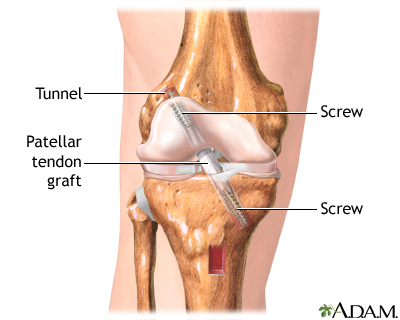

- ǰ�����ʹ���anterior cruciate ligament��ACL��������һ���������˶�������ѵ���������ճ������н�Ϊ����������ϥ�ؽ����ˡ�ACL ����ͨ����������������������������ɽ��ѩ���˶���Ŀ�����������˶�Ա�� ACL ����ռ����ϥ�ؽ����˵� 25.4%��������ѧ�������.....

- ǰ�����ʹ���ACL�������dz�����ϥ�ؽ��ʹ�����֮һ����ͳ��ÿ�귢������1/3000��ǰ�����ʹ����˴�����������˶�ʱ�������Ƿ�����ٱ仯����Ծʽ������������������������������Ŀ�����˻��ư����Ӵ��ԺͷǽӴ��ԣ��ǽӴ���Լռ78%���ݱ���,������ÿ�����ʮ����ACL�ؽ����ؽ����ѡ��������.....

- ǰ�����ʹ��ؽ�������ȫ�桢����ϸ���������ڣ� BuGu�ǿƿ������� ��2020-02-07

- ǰ�����ʹ��ؽ��������������ڣ������ε���Ҫ�����ڣ��������ڿ������̲����ƣ���������û���γ���Ҫ��������ʶ����ʱ�����Լ������ϰ�����ʱ����ʶ���Լ���Ҫ������ѵ���������ڹ�����������߲���ѧ�Ŀ���ѵ����������6��ʱ���Ѵﵽ���εĽ����������ע����ҽ�ƹ�����ϸ�鿴��.....